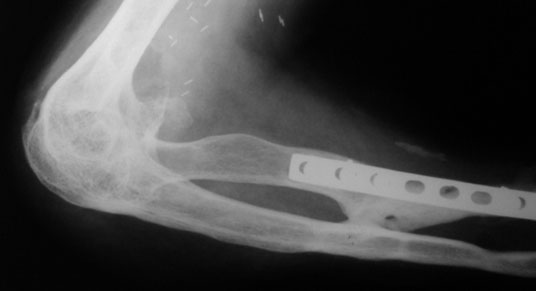

| Xray before surgery | ||

| This 30 year gentleman had been through a lot. He had multiple fractures after a road traffic accident about 5 years ago. He fracture of the right femur, right tibia, both bones of right forearm with fracture of proximal humerus. All open fractures. When he came to us he had a near fused elbow – just a jog of movements. | ||

| The functional outcome after 2 months of surgery. The post surgery arc of motion was 120 degrees with an extension of 20 degrees and flexion up to 130degrees. | ||